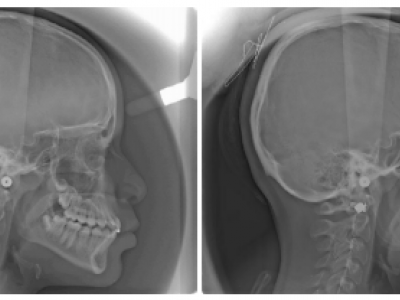

Le patient est revu en denture définitive à 12 ans 9 mois (Fig. 15) avec un bilan radiologique (Fig. 16), pour entreprendre une finition multiattache, les résultats orthopédiques obtenus précocement se sont maintenus.

Le patient est revu à 22 ans 8 mois (Fig. 21-23), à la demande du praticien, avec un bilan radiologique (Fig. 24).